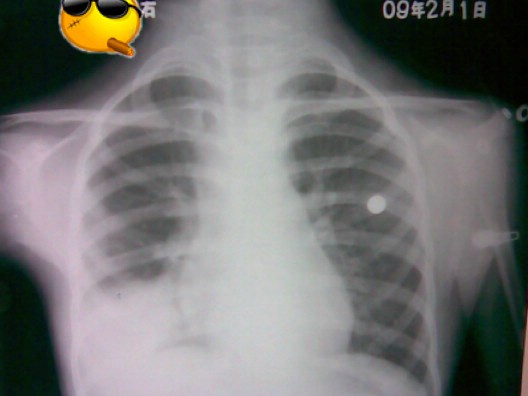

标题: PED1836:女,9岁,发热5天,听诊两肺呼吸音粗 [打印本页]

标题: PED1836:女,9岁,发热5天,听诊两肺呼吸音粗

节段性肺炎。典型!

节段性肺炎。典型!!!

节段性肺炎。片资料完整。